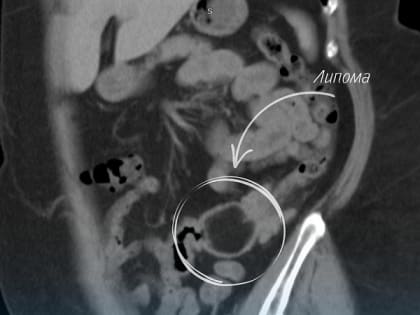

Успешное эндоскопическое удаление липомы у пациента в Нижневартовске

Врачи провели сложную операцию с сохранением целого кишечника.